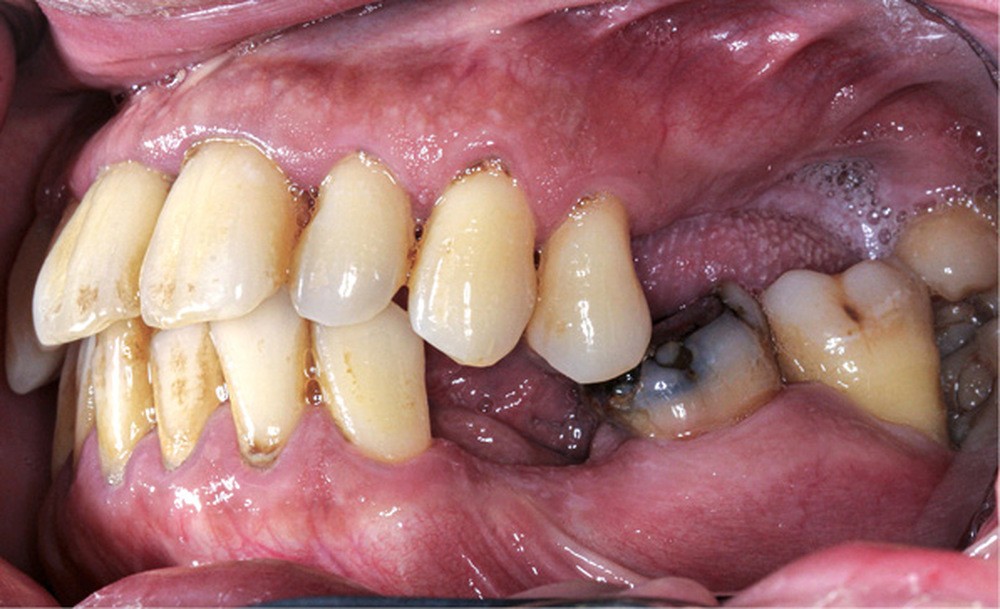

L’obésité, définie par un indice de masse corporelle (IMC) ≥ 30 kg/m2, est une maladie inflammatoire chronique complexe et multifactorielle caractérisée par un dépôt excessif de graisse dans le tissu adipeux. Selon l’OMS, depuis 1975, le nombre de cas d’obésité a presque triplé à l’échelle planétaire [1]. En 2020, près d’un Français sur deux était en surpoids, tandis que 17 % étaient obèses [2]. Or l’obésité est responsable d’une haute mortalité à l’échelle mondiale et est un facteur de risque majeur pour de nombreuses maladies, dont les maladies cardiovasculaires, le diabète de type 2 et certains cancers [1]. Son impact sur la santé des populations et son coût économique et social sont donc considérables. Ces deux dernières décennies, de nombreuses études ont montré que l’obésité pouvait aussi être incriminée dans la détérioration de la santé bucco-dentaire [3] (fig. 1 à 7).